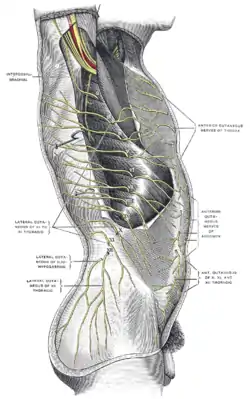

Cutaneous distribution of thoracic nerves. | |

The subcostal nerve (anterior division of the twelfth thoracic nerve[1]) is a mixed motor and sensory nerve contributing to the lumbar plexus. It runs along the lower border of the twelfth rib, often gives a communicating branch to the first lumbar nerve, and passes under the lateral lumbocostal arch.

It then runs in front of the quadratus lumborum, innervates the transversus, and passes forward between it and the abdominal internal oblique to be distributed in the same manner as the lower intercostal nerves.

It communicates with the iliohypogastric nerve and the ilioinguinal nerve of the lumbar plexus,[1][2] and gives a branch to the pyramidalis muscle and the quadratus lumborum muscle.[3] It also gives off a lateral cutaneous branch that supplies sensory innervation to the skin over the hip.